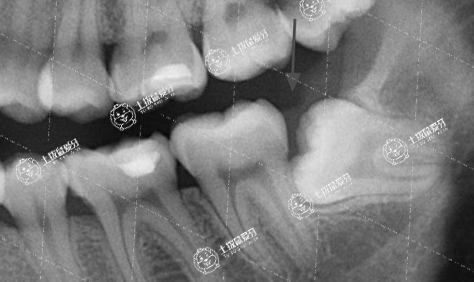

以下智齒是需要拔除的:

1.阻生智齒,已經(jīng)影響了其他牙齒的生長和排列;

⒉發(fā)炎、疼痛的智齒,已經(jīng)影響到健康的智齒;

3.沒有形成良好咬合關(guān)系的智齒,長期下去可能會導(dǎo)致牙齒錯頜畸形。

智齒不正常萌出

1、有些輕中度的牙列擁擠和面型前突,可以通過拔除智齒獲得間隙,解決擁擠和嘴突的問題。

2、阻生智齒反復(fù)的發(fā)炎疼痛的情況,需要盡快拔除。否則在正畸的1-3年的時間里發(fā)炎疼痛反復(fù)發(fā)生,可能導(dǎo)致前面的磨牙被頂壞。預(yù)防性的盡早拔除智齒永遠比亡羊補牢要省時省力省錢得多。

3、拔除阻生的智齒,防止牙齒擁擠復(fù)發(fā),阻生的智齒有一直沿著牙冠方向萌出的力量。所以建議盡快拔除阻生的智齒,防范于未然。